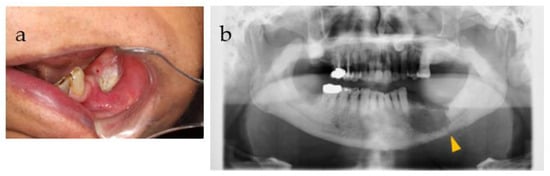

| 0 | First visit (Figure 1), | |||

| biopsy (Figure 2), | PV, peri-implantitis, S/O: gingival malignant tumor | SBCWPV (first) | ||

| start of steroid treatment | ||||

| 7 | (Figure 3) | Significant enlargement of the lesion due to bone melting at tooth 35 | ||